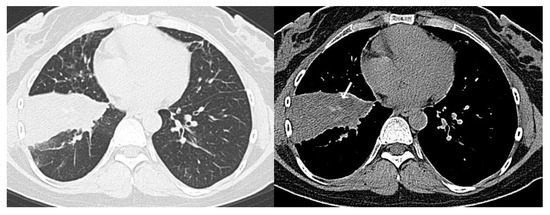

- CO-RADS 4 means a high level of suspicion for pulmonary lesion resulting from COVID-19, based on typical CT findings but exhibiting some overlap with other types of (viral) pneumonia. Findings are not located in contact with the visceral pleura or are located strictly unilaterally, have a predominantly peribronchial distribution, or overlap with severe diffuse preexisting pulmonary abnormalities.